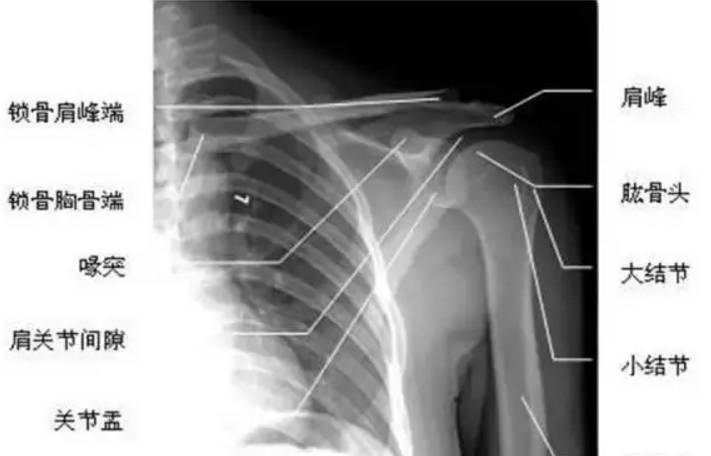

肩峰骨骺x线图片,儿童肩关节骨骺线图片

儿童肩关节骨骺线图片

肩关节骨骼

小儿肩关节x线图片

小儿肩关节正常x光片

肩关节x线图片